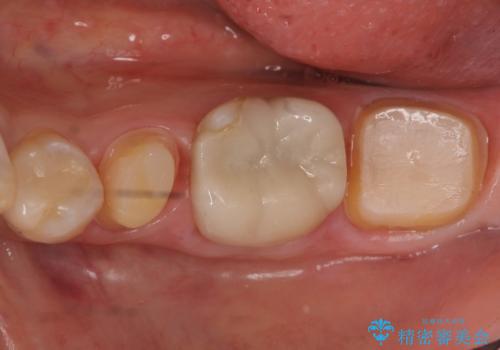

2. 昔いれたクラウンが割れたので金属の被せ物を入れたいの治療中

2.